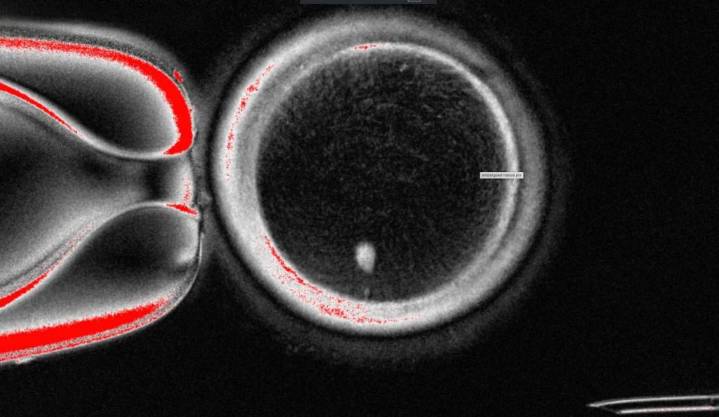

WASHINGTON (AP) — Oregon scientists used human skin cells to create fertilizable eggs, a step in the quest to develop lab-grown eggs or sperm to one day help people conceive.

But the experiment resulted in abnormalities in the chromosomes, prompting the Oregon Health & Science University team to caution it could take a decade of additional research before such a technique might be ready for trials in people.

The OHSU team removed the nucleus from a human egg cell and replaced it with the nucleus from a human skin cell. But a skin cell contai